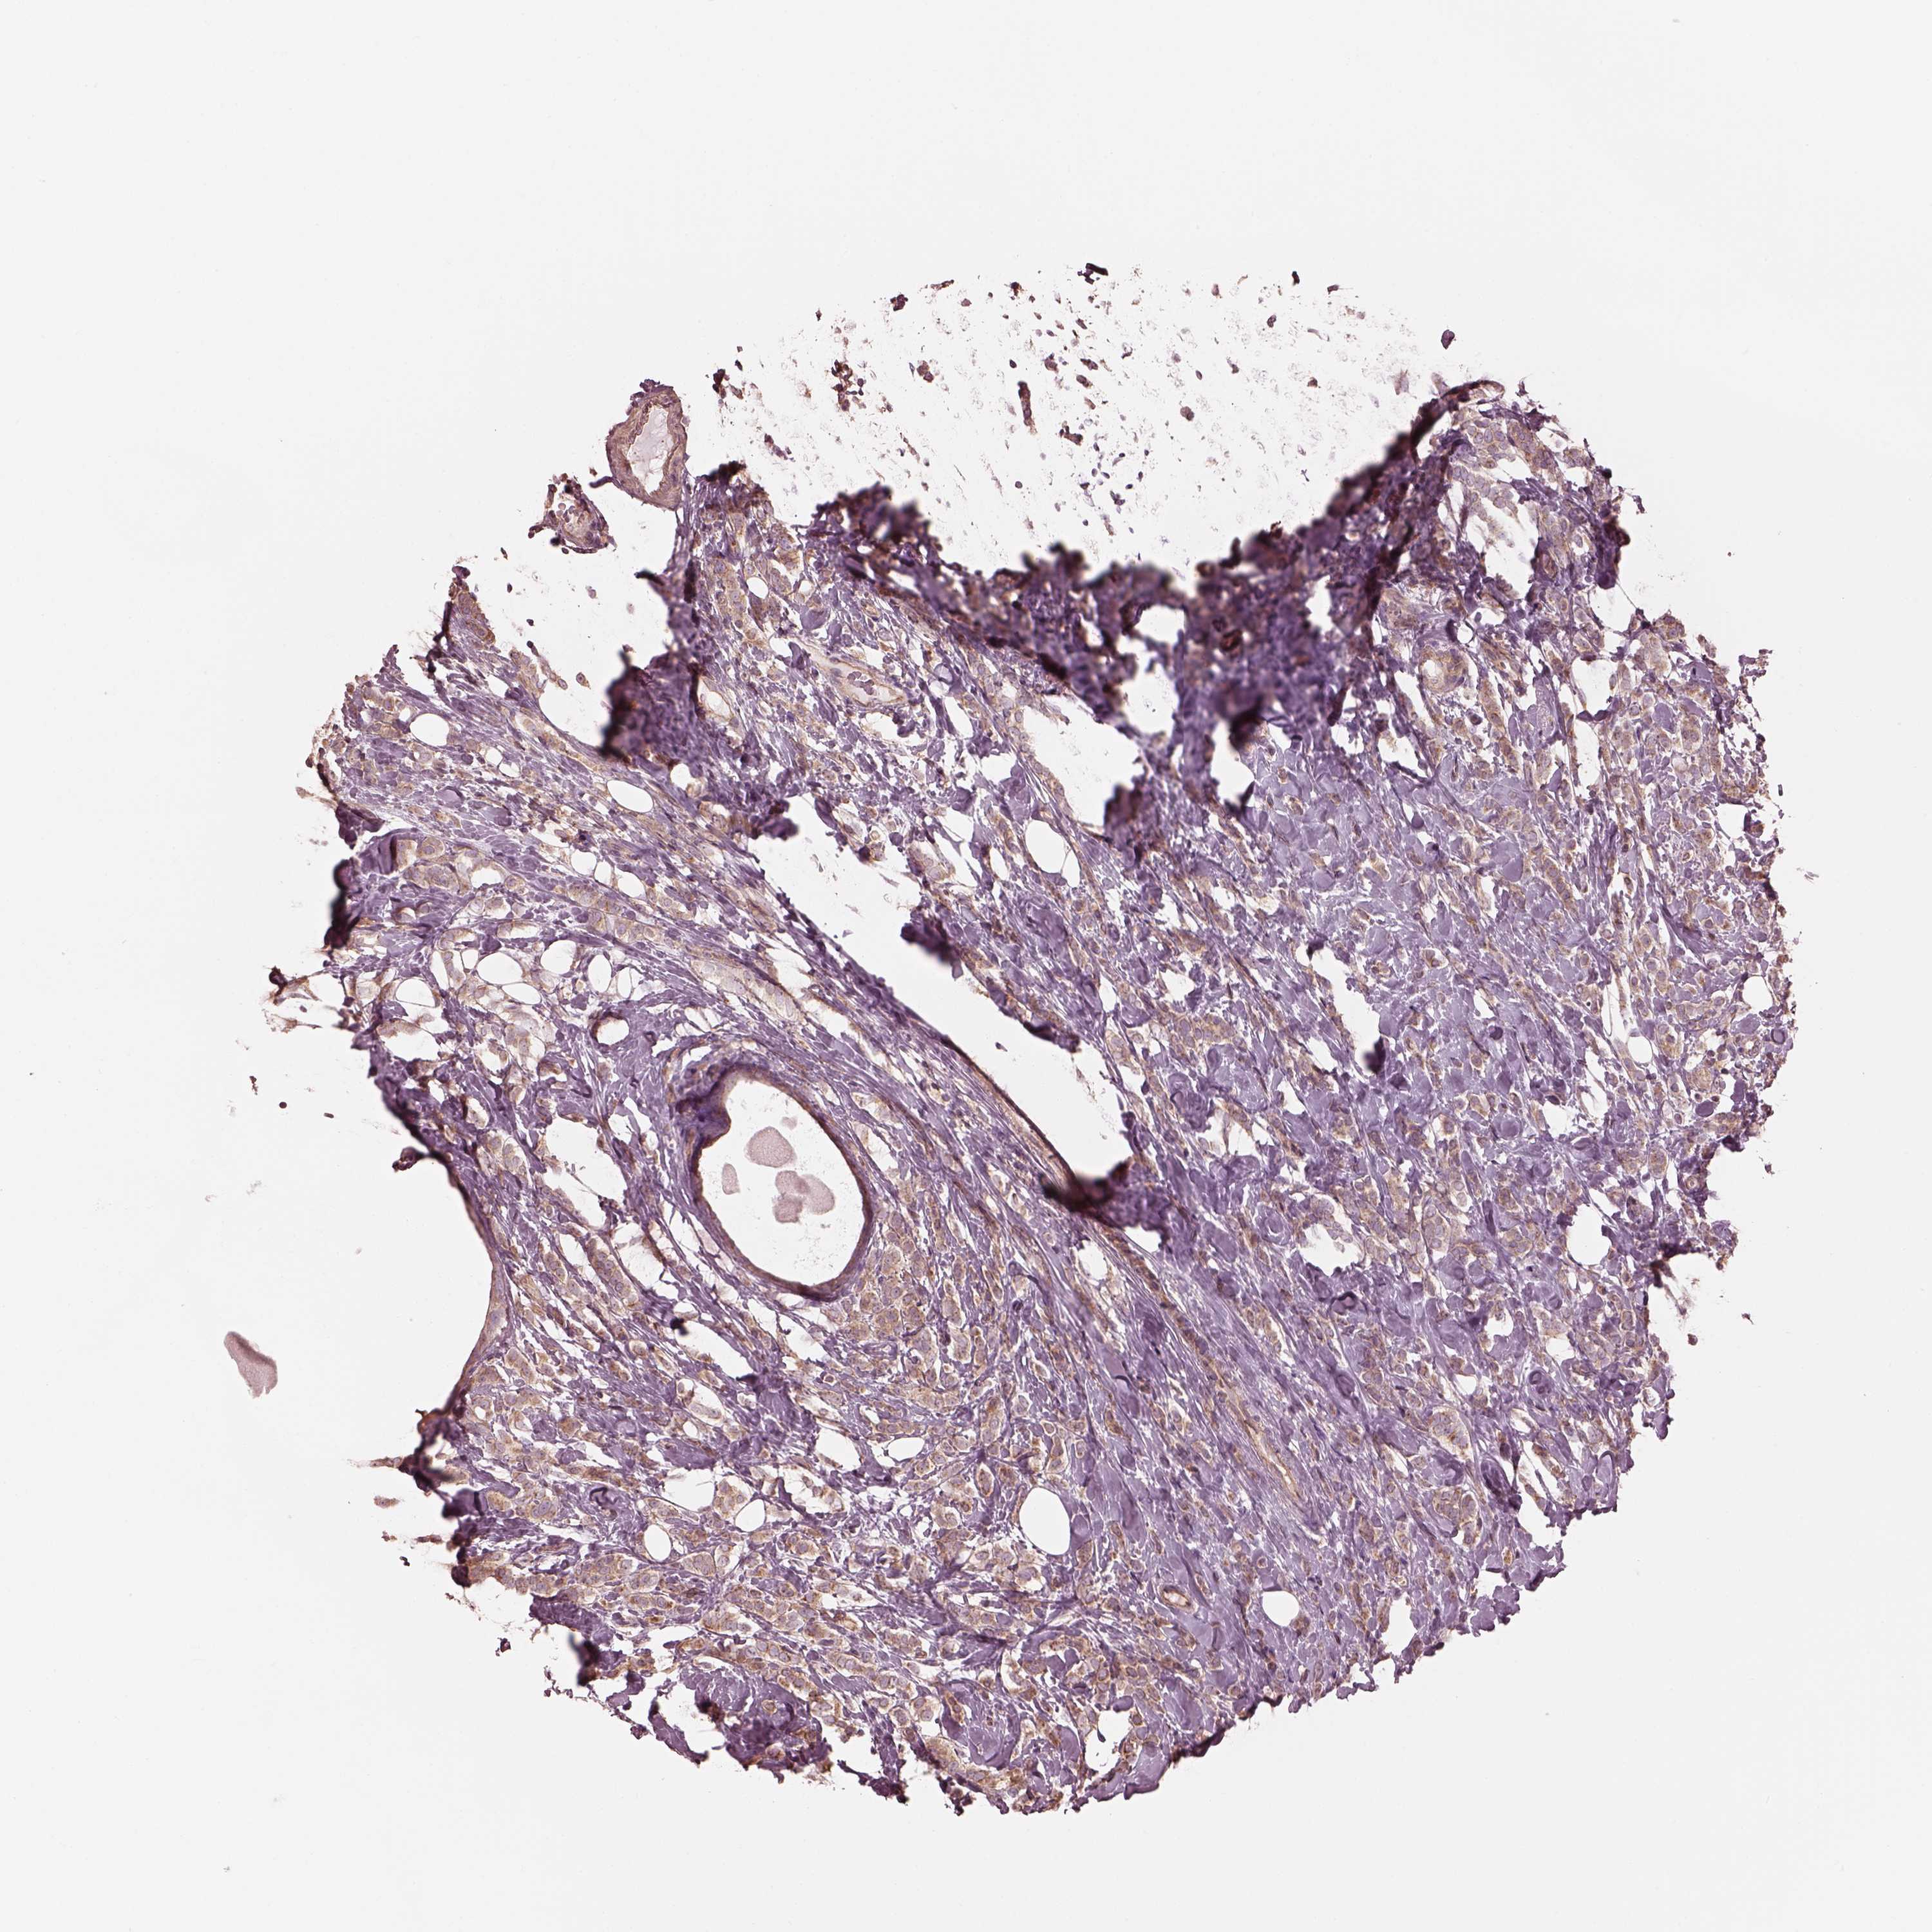

BRCA TCGA BRCA VALIDATION PROTEIN EXPRESSION